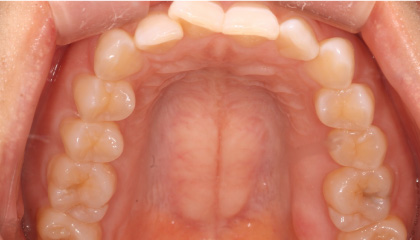

Before

-

After

※患者さまの治療ゴール(イメージ)を精度高く理解することを得意とする当院では、上顎は治療を行わず下顎のみの治療としました。結果、期間・費用を適正化することができ、患者さまのゴールイメージに合った治療となりました。